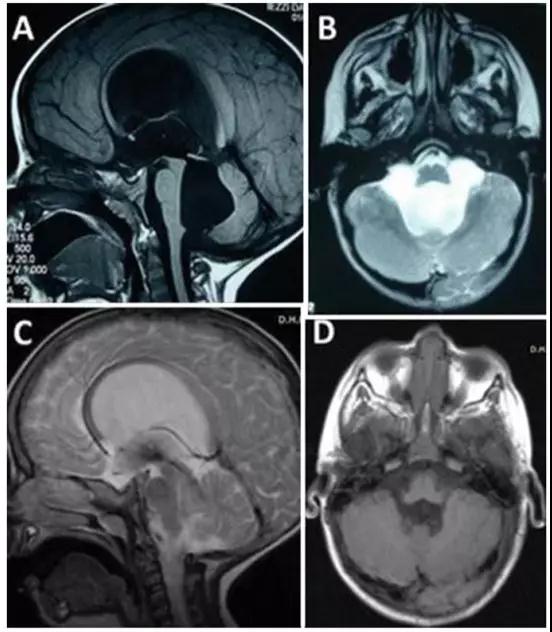

脑积水治疗预后怎么样?脑积水什么时候需要手术?

脑积水是一种过量的脑脊液(CSF)在脑室(含液体的腔)内积聚并可能增加头部压力的疾病。神经外科中比较常见,它的原因多种多样。虽然脑积水常被描述为脑中的水,但水实际上是脑脊液...